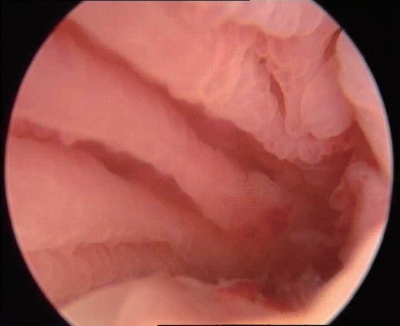

③分泌期子宫内膜:内膜往往呈半球状或息肉样突起,水肿样改变,半透明白色或黄白色,可清晰透见毛细血管网,皱褶减少变浅,腺体开口难辨(图3-7)。